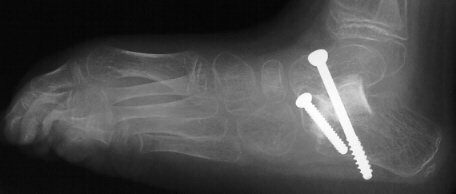

Postoperative X-rays:

- Left Talocalcaneal angle is 24 degrees, Talonavicular angle is 2 degrees

- Right Talocalcaneal angle is 28 degrees, Talonavicular angle is 2 degrees